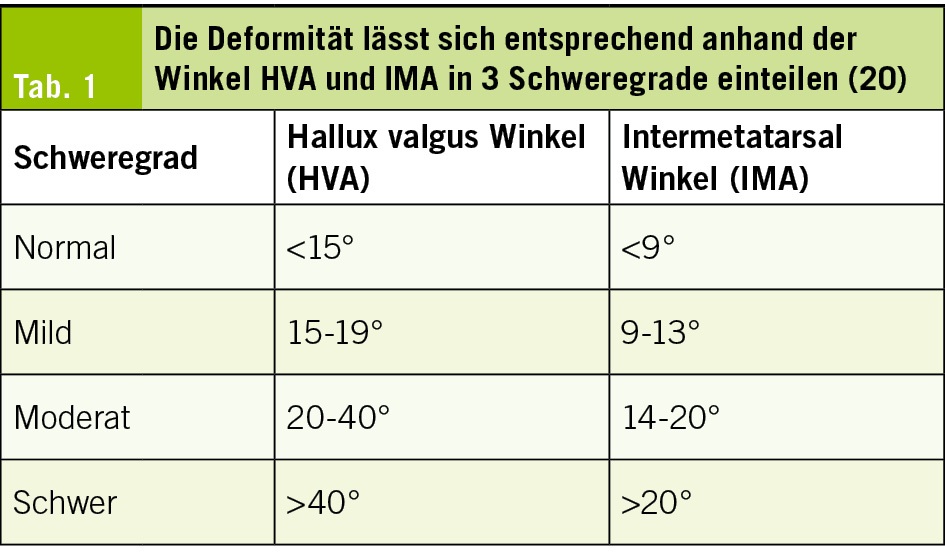

Als primär diagnostisches Tool wird das konventionelle belastete Röntgenbild durchgeführt (6, 16, 17). Es können einige radiologische Winkel bestimmt werden, so zum Beispiel zwischen dem Schaft des Metarsale I und dem Schaft der proximalen Phalanx, dies ist der klassische Hallux valgus Winkel (HVA), der Winkel zwischen den ersten beiden Metatarsale (IMA) und der Winkel zwischen den Phalangen (HVI) (Abb. 3). Schnittbildgebungen wie MRI oder CT werden im Normalfall nicht benötigt. Ein MRI wird jedoch durchgeführt, wenn zum Beispiel der Knorpelzustand am MTP I beurteilt werden muss, da schon eine Arthrose bestehen könnte oder wenn Schmerzen in den Zwischenzehenräumen bestehen und ein Mortonneurom vermutet wird (18). Zunehmend können auch stehende CT Bildgebungen durchgeführt werden, dies zum einen um die Rotation des Metatarsale und die Position der Sesambeine genauer beurteilen zu können, zum anderen gibt es eine sehr potente Übersicht des Fusses unter Belastung, was die präoperative Vorbereitung stark präzisieren kann (19).